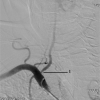

The A.N. Kazantsev artery is a vessel starting from the common carotid artery with subsequent bifurcation into 2 vessels of equal size-the internal carotid artery (ICA) and the persistent embryonic hypoglossal artery (PEHA). Until now, this artery has been considered as the ICA. However, according to all existing classifications, the ICA in the cervical segment does not have arterial branches. In addition, in view of the comparable sizes of PEHA and ICA, PEHA itself cannot be considered a branch of the ICA. Thus, by the right of the first description, the authors of the article named this vascular formation as the A.N. Kazantsev artery, which forms a bifurcation of the PEHA and ICA. In this clinical case, carotid angioplasty (CAS) was performed with stenting of 80% stenosis of the A.N. Kazantsev artery in the most acute period of acute cerebrovascular accident (ACV). According to angiography, the following was also revealed: the presence of PEHA, extending from the A.N. Kazantsev artery 5 cm above its mouth, connecting with the main artery; stenosis of the right vertebral artery 60% at the mouth; hypoplastic left vertebral artery with aplasia of the V4 segment; open circle of Willis (VC): absence of both posterior communicating arteries (PCA). Due to the high risk of recurrent CVA due to clamping of the A.N. Kazantsev artery during CEA, a multidisciplinary consultation decided to implement an emergency CAS of the A.N. Kazantsev artery. The distal embolism protection system FilterWire was inserted into the proximal part of the basilar artery through the radial artery on the left. The distal embolism protection system RX Accunet was inserted into the distal parts of the left ICA through the left common femoral artery. According to Seldinger, an Acculink stent 7-10 × 30 mm was inserted into the affected area of the A.N. Kazantsev artery, positioned and opened. The postoperative period was uneventful. ACV did not recur. Conducted dual antiplatelet therapy (acetylsalicylic acid 125 mg in the afternoon + clopidogrel 75 mg in the morning). The patient was discharged from the institution on the 10th day after the operation in a satisfactory condition.